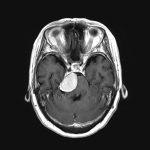

712

'25年12月

70代

下垂体腫瘍

頭蓋内腫瘍摘出術

No.’25_114 手術前1

No.’25_114 手術前2

No.’25_114 摘出 前

No.’25_114  摘出 中

No.’25_114 摘出 後